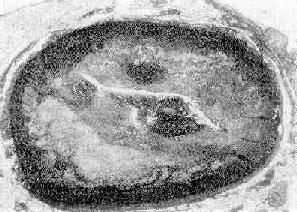

病变特点:粥样硬化斑块的分布多在近侧段,且在分支口处较重;早期,斑块分散,呈节段性分布,随着疾病的进展,相邻的斑块可互相融合。在横切面上斑块多呈新月形,管腔呈不同程度的狭窄。有时可并发血栓形成,使管腔完全阻塞(图8-28,图8-29)。根据斑块引起管腔狭窄的程度可将其分为4级:Ⅰ级,管腔狭窄在25%以下;Ⅱ级,狭窄在26%~50%;Ⅲ级,狭窄51%~75%;Ⅳ级,管腔狭窄在76%以上。

图8-28 冠状动脉粥样斑块并发血栓形成

图示左前降支粥样斑块,累及动脉壁四周,斑块底部粥样物中含大量胆固醇结晶;管腔被血栓阻塞(男性,50岁)

图8-29示图8-28管腔内血栓的放大,主要为白色血栓(↑);右下为纤维素